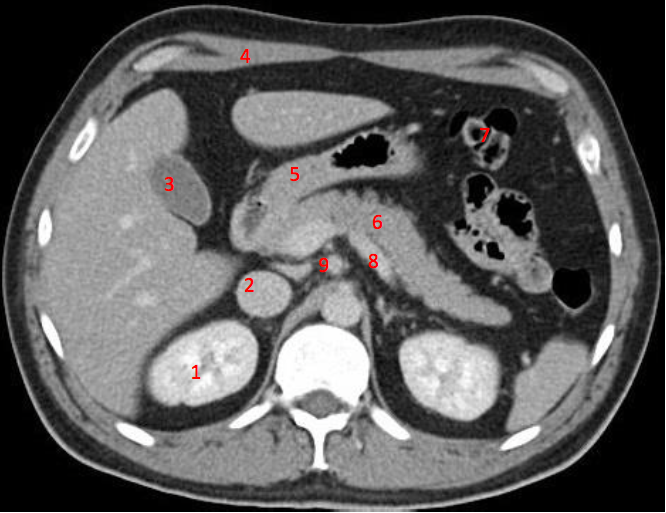

1

Number 3?

IVC

2

Number 1?

R Kidney

3

Q

A

4

Perfectly

How well did you know this?

Not at all

5